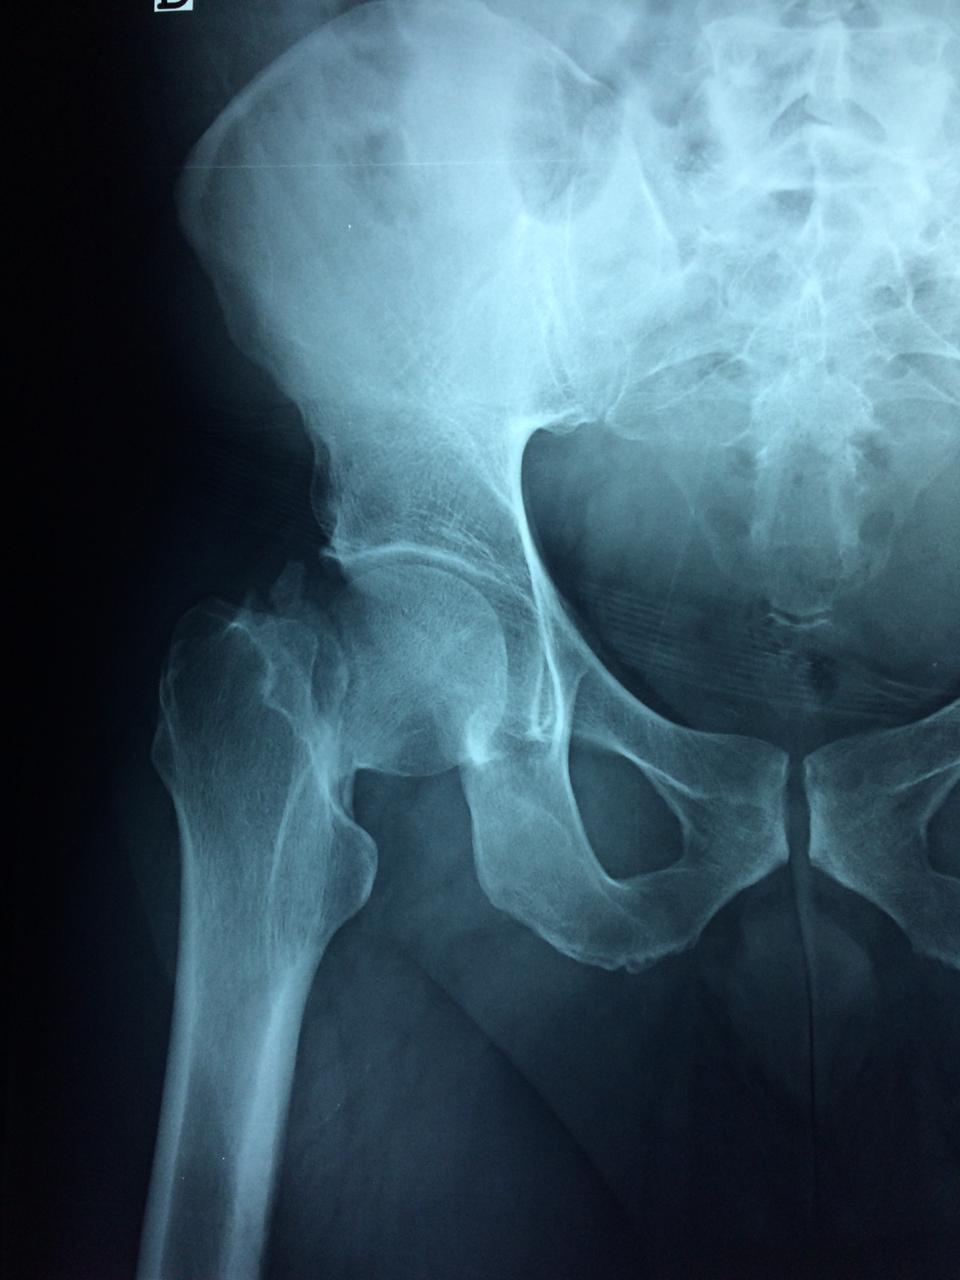

La cirugía de fractura de cadera se realiza para reparar una ruptura en la parte superior del hueso del muslo. Este hueso se denomina fémur.

Es parte de la articulación coxofemoral. Si una fractura de cadera no recibe tratamiento, es posible que deba permanecer en una silla o en la cama.